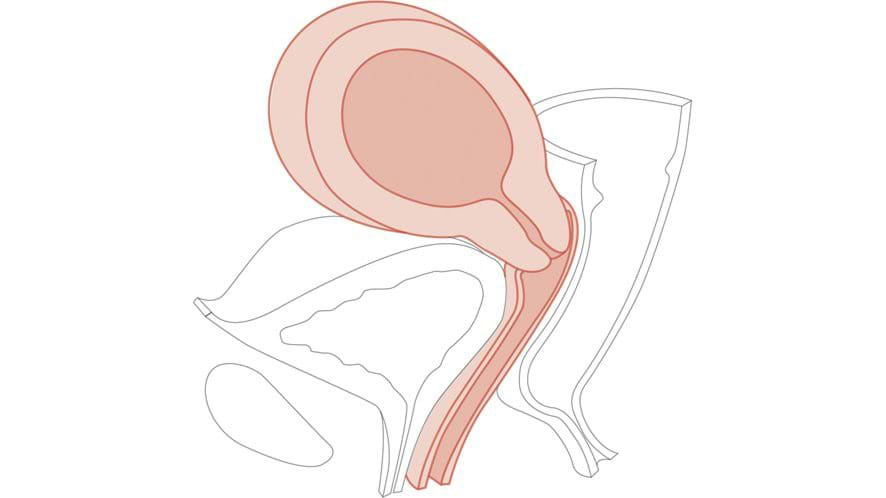

10-12 weeks pregnant module for use with the Limbs & Things CFPT Mk3 ALT60905 Advanced and ALT60900 Standard.

- As part of the Clinical Female Pelvic Trainer Mk3 for hands-on examination experience